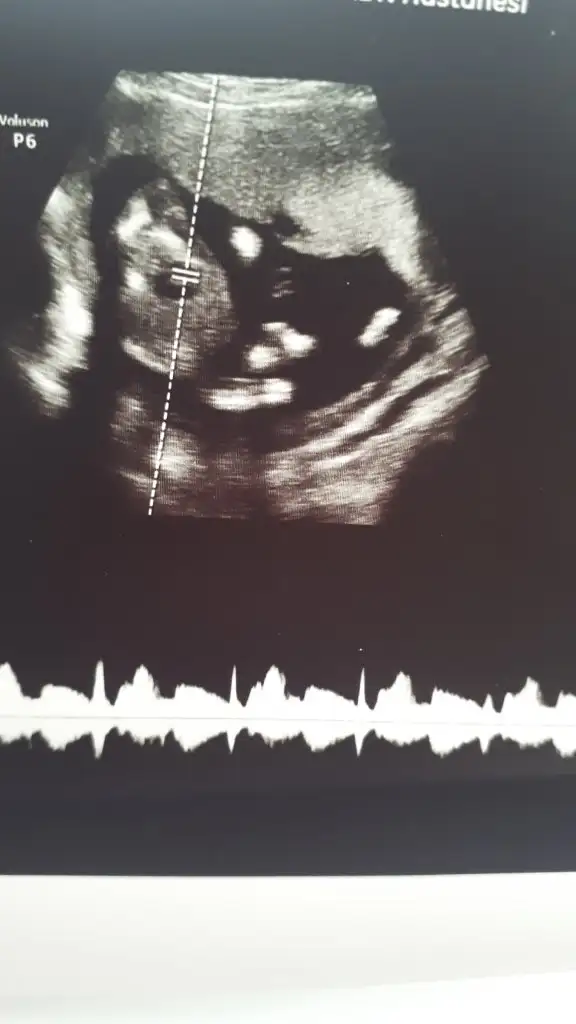

dr soylemeden siz gorun genital nub teorisi ( bebegin cinsiyeti)

Arkadaşlar lutfen tahmin eder misiniz

Doktorumun söylediği bir tüyomda var cinsiyet tahmini ile ilgili. Varsa daha keseyi gördüğünüz zaman ki ultrasonlarınız yardımcı olurum😘

5 haftalıkken kese şekli yuvarlaksa kız,yanlardan içe doğru baskın yani fasülyeye benziyorsa erkek. Bende ve akrabalarımda tuttu bu teorisi doğru yanlış bilemiyorum 😄